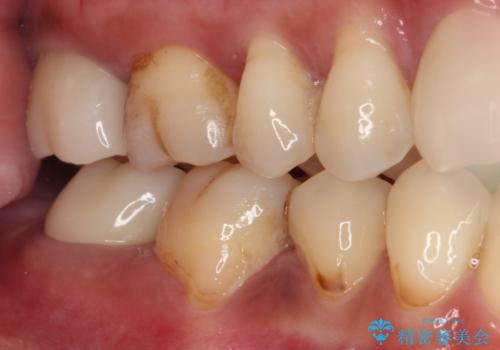

既に神経は失活していましたが根管治療はされておらず、むし歯が大きかったためか、歯全体が手前に動いてしまっていました。

前方に傾斜したまま補綴治療を行うと、歯間にものが挟まりやすい上に、歯間ブラシなどの清掃器具も通しにくくなるため、清掃性が著しく低下します。